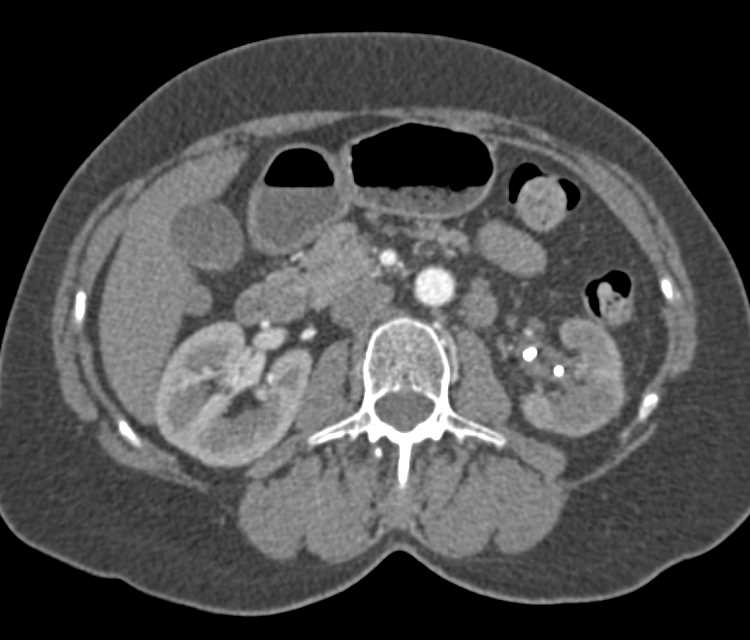

Paraganglioma